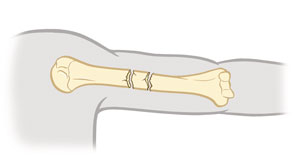

Spiral fracture

The break spirals around the bone. This is common in a twisting injury.